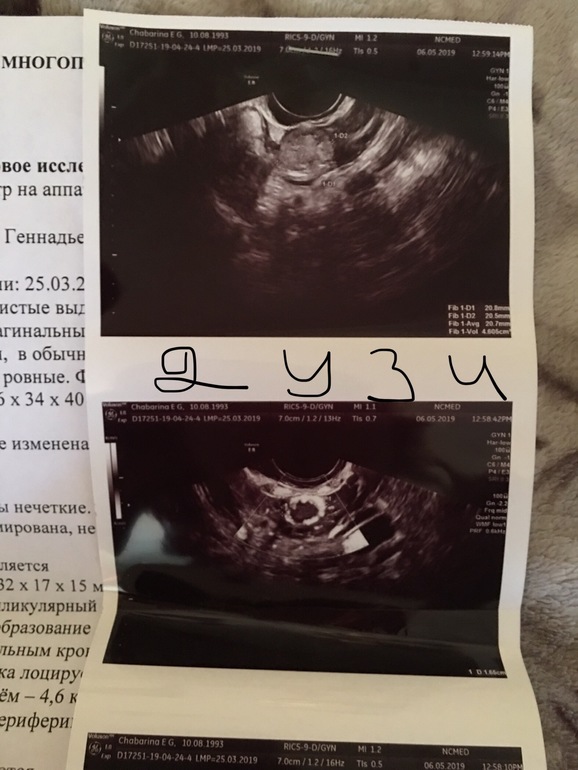

Вопросы про УЗИ, обследования и анализы: что, где, как, когда?Добрый день , я у вас новенькая ) задержка 2 недели , на первой недели была на узи и сейчас . При первом ставили маточную, сейчас внематочную . Помогите разобраться 🙏🏻😩 фото под катом .

К сожалению... 90% - внематочная... так как при ней очень часто бывает ложное плодное яйцо в матке.. у меня именно так и было. 1.9 мм - «пя» и через неделю на узи внематочная в левой трубе

Недавно на сайте такая же история у девушки была. И на узи первом увидели пя. Ошибка узиста. Врачи плохие, это беда. И хгч у вас падает, я так поняла??? А что с выделениями????

Хгч да , в 7 дней задержки был 899, на 11 день задержки 598 , выделения были светло коричневые , поехала сразу в больницу - два раза сделали осмотр с зеркалом и пошли почти чёрные с очень мелкими как точка сгустками . Ни капельниц , ни уколов . Ни анализов . Сбежала оттуда сразу на хгч . Всю неделю пью транескам и дюфастон 😟

Вот на втором узи написано что что то около яичника 21 мм , разве мог так вырасти ?